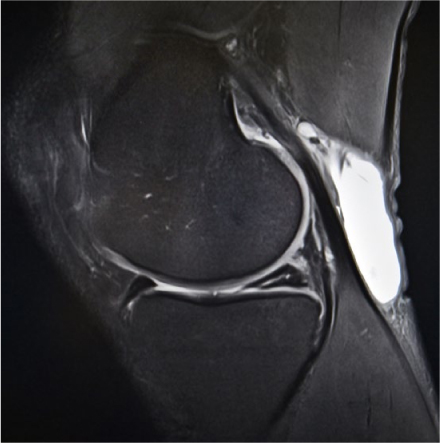

Huisartsen krijgen vaak patiënten op het spreekuur die knieklachten hebben na een doorgemaakt trauma. Huisartsen kunnen voor deze patiënten direct een MRI-scan aanvragen. Bij 18- tot 45-jarige patiënten met traumatische knieklachten is zo'n MRI niet kosteneffectief. De scan leidde bij deze groep tot hogere zorgkosten, zonder verbetering van de kwaliteit van leven.